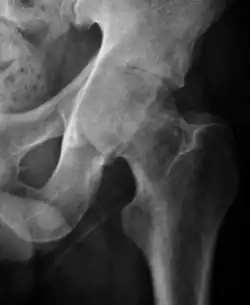

Projectional radiography ("X-ray") is the first imaging technique of choice in hip pain, not only in older people with suspected osteoarthritis but also in young people without any such suspicion. In this case plain radiography allows categorization as normal hip or dysplastic hip, or with impingement signs, pincer, cam, or a combination of both.[1]

X-Ray

Projectional radiography ("X-ray") is currently useful not only in older people in whom osteoarthritis of the hip is suspected but also in younger people without osteoarthritis, who are being evaluated for femoroacetabular impingement (FAI) or hip dysplasia.[1]

Plain radiography allows us to categorize the hip as normal or dysplastic or with impingement signs (pincer, cam, or a combination of both). Besides these, pathologic processes like osteoarthritis, inflammatory diseases, infection, or tumors can also be identified (Figure 1).[1]

Figure 1.

-

Radiography in normal hip -

X-ray in pincer impingement type of hip dysplasia -

X-ray of cam -

Hip in osteoarthritis -

Septic arthritis

X-ray in pediatrics